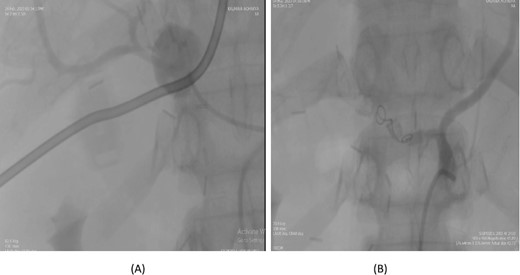

A 66-year-old male underwent an extended cholecystectomy with bile duct excision and Roux-en-Y hepaticojejunostomy for suspected gallbladder carcinoma. However, the histopathological examination revealed xanthogranulomatous cholecystitis. Postoperative patient develops anastomotic site leakage so was discharged with abdominal drain. On the 9th postoperative day, during follow-up for bile leak with an abdominal drain in situ, a contrast-enhanced CT scan of the abdomen identified a pseudoaneurysm at the bifurcation of the gastroduodenal artery and proper hepatic artery. Angioembolization was performed using two coils and 50% glue. The abdominal drain was subsequently removed, and the patient recovered without further complications, doing well at follow-up (Fig. 4).

Case 4. (A) CT scan – pseudoaneurysm at bifurcation of gastroduodenal artery and proper hepatic artery. (B) Embolization of gastroduodenal artery and proper hepatic artery.